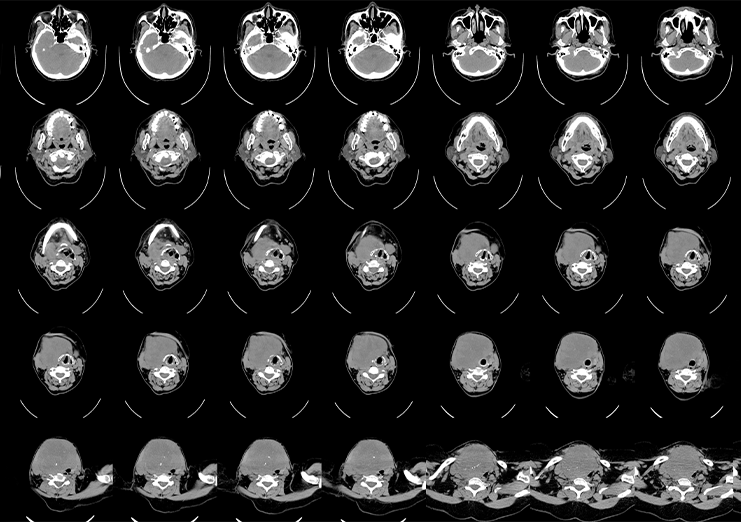

Case Example: A healthcare AI company developing lung cancer detection models faced challenges in handling large-scale CT scan data. NextWealth deployed domain-trained annotators with radiology-specific SOPs, delivering pixel-precise annotations.

Impact Delivered:

99%+ annotation accuracy across thousands of scans

30% reduction in AI model training cycles

Accelerated FDA approval support through reliable datasets